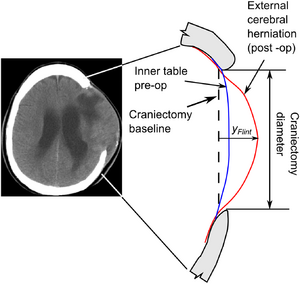

A New Improved Method for Assessing Brain Deformation after Decompressive Craniectomy

Publication: PLoS One. 2014 Oct 10;9(10):e110408. PMID: 25303305 | PDF Authors: Fletcher TL, Kolias AG, Hutchinson PJ, Sutcliffe MP. Institution: Department of Engineering, University of Cambridge, Cambridge, UK. Background/Purpose: Decompressive craniectomy (DC) is a surgical intervention used following traumatic brain injury to prevent or alleviate raised intracranial pressure. However the clinical effectiveness of the intervention remains in doubt. The location of the craniectomy (unilateral or bifrontal) might be expected to change the brain deformation associated with the operation and hence the clinical outcome. As existing methods for assessing brain deformation have several limitations, we sought to develop and validate a new improved method. Funding: